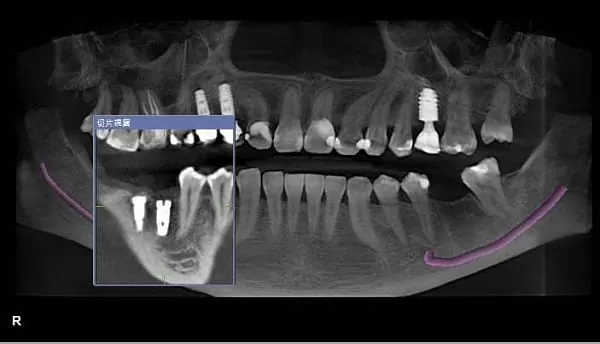

(圖4) 3D全口影像,可清楚呈現下顎神經管,紫線表示神經管

植牙前在「口腔狀況的判讀」是非常重要的,傳統平面全口X光片簡稱PANO,它們「只能顯現平面影像,無法展示口腔狀況的切面與橫斷面,容易造成骨質與骨量判讀上的誤差。CT則是呈現3D影像,並且有一個專屬的視窗(圖5),可以很清楚地往舌側的方向橫切過去,讓橫切面全部顯現出來。當醫師在與病人解說時,可以移動視窗顯示病人骨質的寬度及神經管的位置,另外可置入虛擬植體圖示(圖6),讓病人更清楚明白醫師的解說以及要為他植牙的位置及角度。